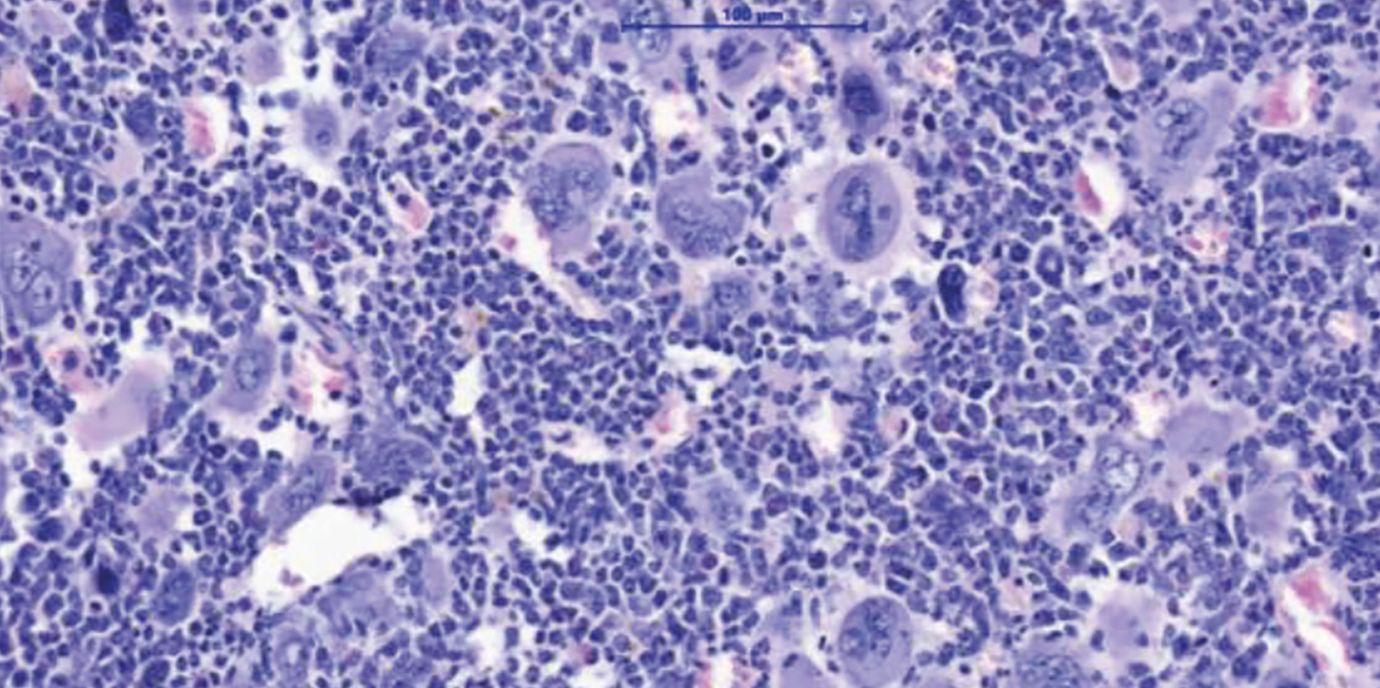

Myeloproliferative Neoplasien (MPN) sind Blutkrebserkrankungen, die durch eine Überproduktion von Blutzellen gekennzeichnet ist. Diese Erkrankungen treten in der Regel ab einem Alter von 60+ Jahren auf und können über lange Zeit gut kontrolliert werden. Gefährlich werden MPN vor allem nach dem Übergang in eine Myelofibrose – eine lebensbedrohliche Vernarbung des Knochenmarks. Eine allogene Stammzelltransplantation bietet für die betroffenen Patient:innen bis heute die einzige Aussicht auf Heilung. „Wir brauchen dringend neue Therapiekonzepte. Eine Stammzell-Transplantation ist für viele Patient:innen aufgrund ihres hohen Alters oder wegen Begleiterkrankungen mit zu hohen Risiken verbunden“, erklärt Dominik Wolf, Direktor der Univ.-Klinik für Innere Medizin V (Hämatologie und Onkologie) an der Medizinischen Universität Innsbruck, den Hintergrund einer soeben im Fachjournal Nature Communications hochrangig publizierten Forschungsarbeit, die er konzipiert und gemeinsam mit Lino Teichman und Miriam Körber vom UKBonn durchgeführt hat. „Wir zeigen in dieser Arbeit ein mögliches neues Therapiekonzept auf, das man klinisch weiterentwickeln sollte“, sagt Wolf, der gemeinsam mit Lino Teichmann als Letzt- und korrespondierender Autor firmiert. Den Wissenschafter:innen ist es gelungen, das NLRP3-Inflammason im Tiermodell zu hemmen und dadurch deutliche Verbesserungen des Krankheitsverlaufs zu erzielen: Die Knochenmarksvernarbung und die Milzvergrößerung bildeten sich zurück und das Blutbild verbesserte sich.

Konkret haben sich die Autor:innen mit den Mechanismen der Entzündungsreaktion bei MPN beschäftigt, da diese zu vielen klinischen Symptomen und letztlich auch zur Vernarbung des Knochenmarks führt. Das NLRP3-Inflammasom ist ein Sensor für Gefahrensignale, der Entzündungsprozesse im Körper steuert und dessen Bedeutung bereits eingehend bei chronischen Entzündungserkrankungen wie Atherosklerose, Gicht oder auch Diabetes Typ-2 studiert wurde. Bei MPN wird die Entzündung in den bösartigen, aber auch in den begleitenden, noch gesunden Blutzellen von einer genetischen Treibermutation ausgelöst, wobei hier die aktivierende Mutation JAK2V617F eine zentrale Rolle spielt.

„Wir haben eng mit Eicke Latz, dem Leiter des Deutschen Rheuma-Forschungszentrums in Berlin, kooperiert, der uns verschiedenste Tools zur Verfügung gestellt hat. Damit konnten wir zeigen, dass diese Entzündungsfaktoren wirklich in Abhängigkeit von NLRP3 produziert werden. Besonders interessant war, dass wir das NLRP3 genetisch in Knockout-Mäusen und auch mithilfe eines neuartigen und spezifischen NLRP3-inhibierenden Medikaments hemmen konnten“, spricht Wolf einen möglichen Therapieansatz an. Dank IFM-2384, einer Substanz, die ebenfalls von Eicke Latz bereitgestellt wurde, konnte im Tiermodell eine deutliche Verbesserung erzielt werden. „Die Knochenmarksvernarbungen und auch die meistens sehr ausgeprägten Milzvergrößerungen gingen zurück. Wir konnten auch das Blutbild verbessern“, zählt Wolf auf.